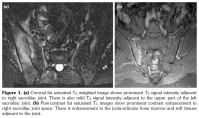

On detailed questioning, he had no history of recent urinary tract infection, acute gastroenteritis, uveitis or sexually transmitted diseases. He had a sharp pain which localized on right greater trochanter extending to his posterior thigh. He reported approximately one hour of stiffness in the right hip. His body temperature was 37.2 °C, pulse rate and blood pressure measurements were normal. At physical examination, active and passive right hip movements and sacroiliac compression test were painful. Physical examination was otherwise normal. Laboratory tests showed normal complete blood count with elevated erythrocyte sedimentation rate (53 mm/h) and C-reactive protein (8.80 mg/L). Rheumatoid factor was negative. He had a positive throat culture for beta-hemolytic streptococcus which was performed at the initial hospital, but we wanted to confirm the antecedent streptococcal infection and investigated the serum antistreptolysin O (ASO) titer. It was 1097 IU/mL and 1806 IU/mL on admission and two weeks later, respectively. Human leukocyte antigen B27 test was positive. Liver, renal function tests and urinalysis were normal. Anti cytomegalovirus immunoglobulin M, antinuclear antibody, Venereal Disease Research Laboratory, Treponema pallidum hemagglutination assay, gonorrhea and Brucella agglutination tests were negative. Echocardiography and blood cultures were unremarkable. Plain X-rays showed normal hip joints with suspicious right sacroiliitis. Hence, we performed sacroiliac joint magnetic resonance imaging which revealed acute sacroillitis at the right sacroiliac joint (Figure 1). Accordingly, he was diagnosed as PSReA and acemetacin 60 mg twice daily was prescribed. On the third week control visit, the patient was found to have improved significantly with decreased pain and normalized laboratory test results. Equally, ASO titer reached normal values after treatment.

Poststreptococcal reactive arthritis is a type of non-migratory arthritis that usually affects the knee and ankle joints, and axial involvement is rare.(3) To our best notice, sacroiliitis and adductor muscle involvement has been reported in a few cases in PSReA.(4) We established the diagnosis by demonstrating the unilateral sacroiliitis and the adductor enthesopathy with magnetic resonance imaging. Likewise, we would like to draw attention of physicians towards the possibility of sacroiliitis in patients with PSReA. Substantial medical history, prompt physical examination and imaging would definitely be crucial in this regard.